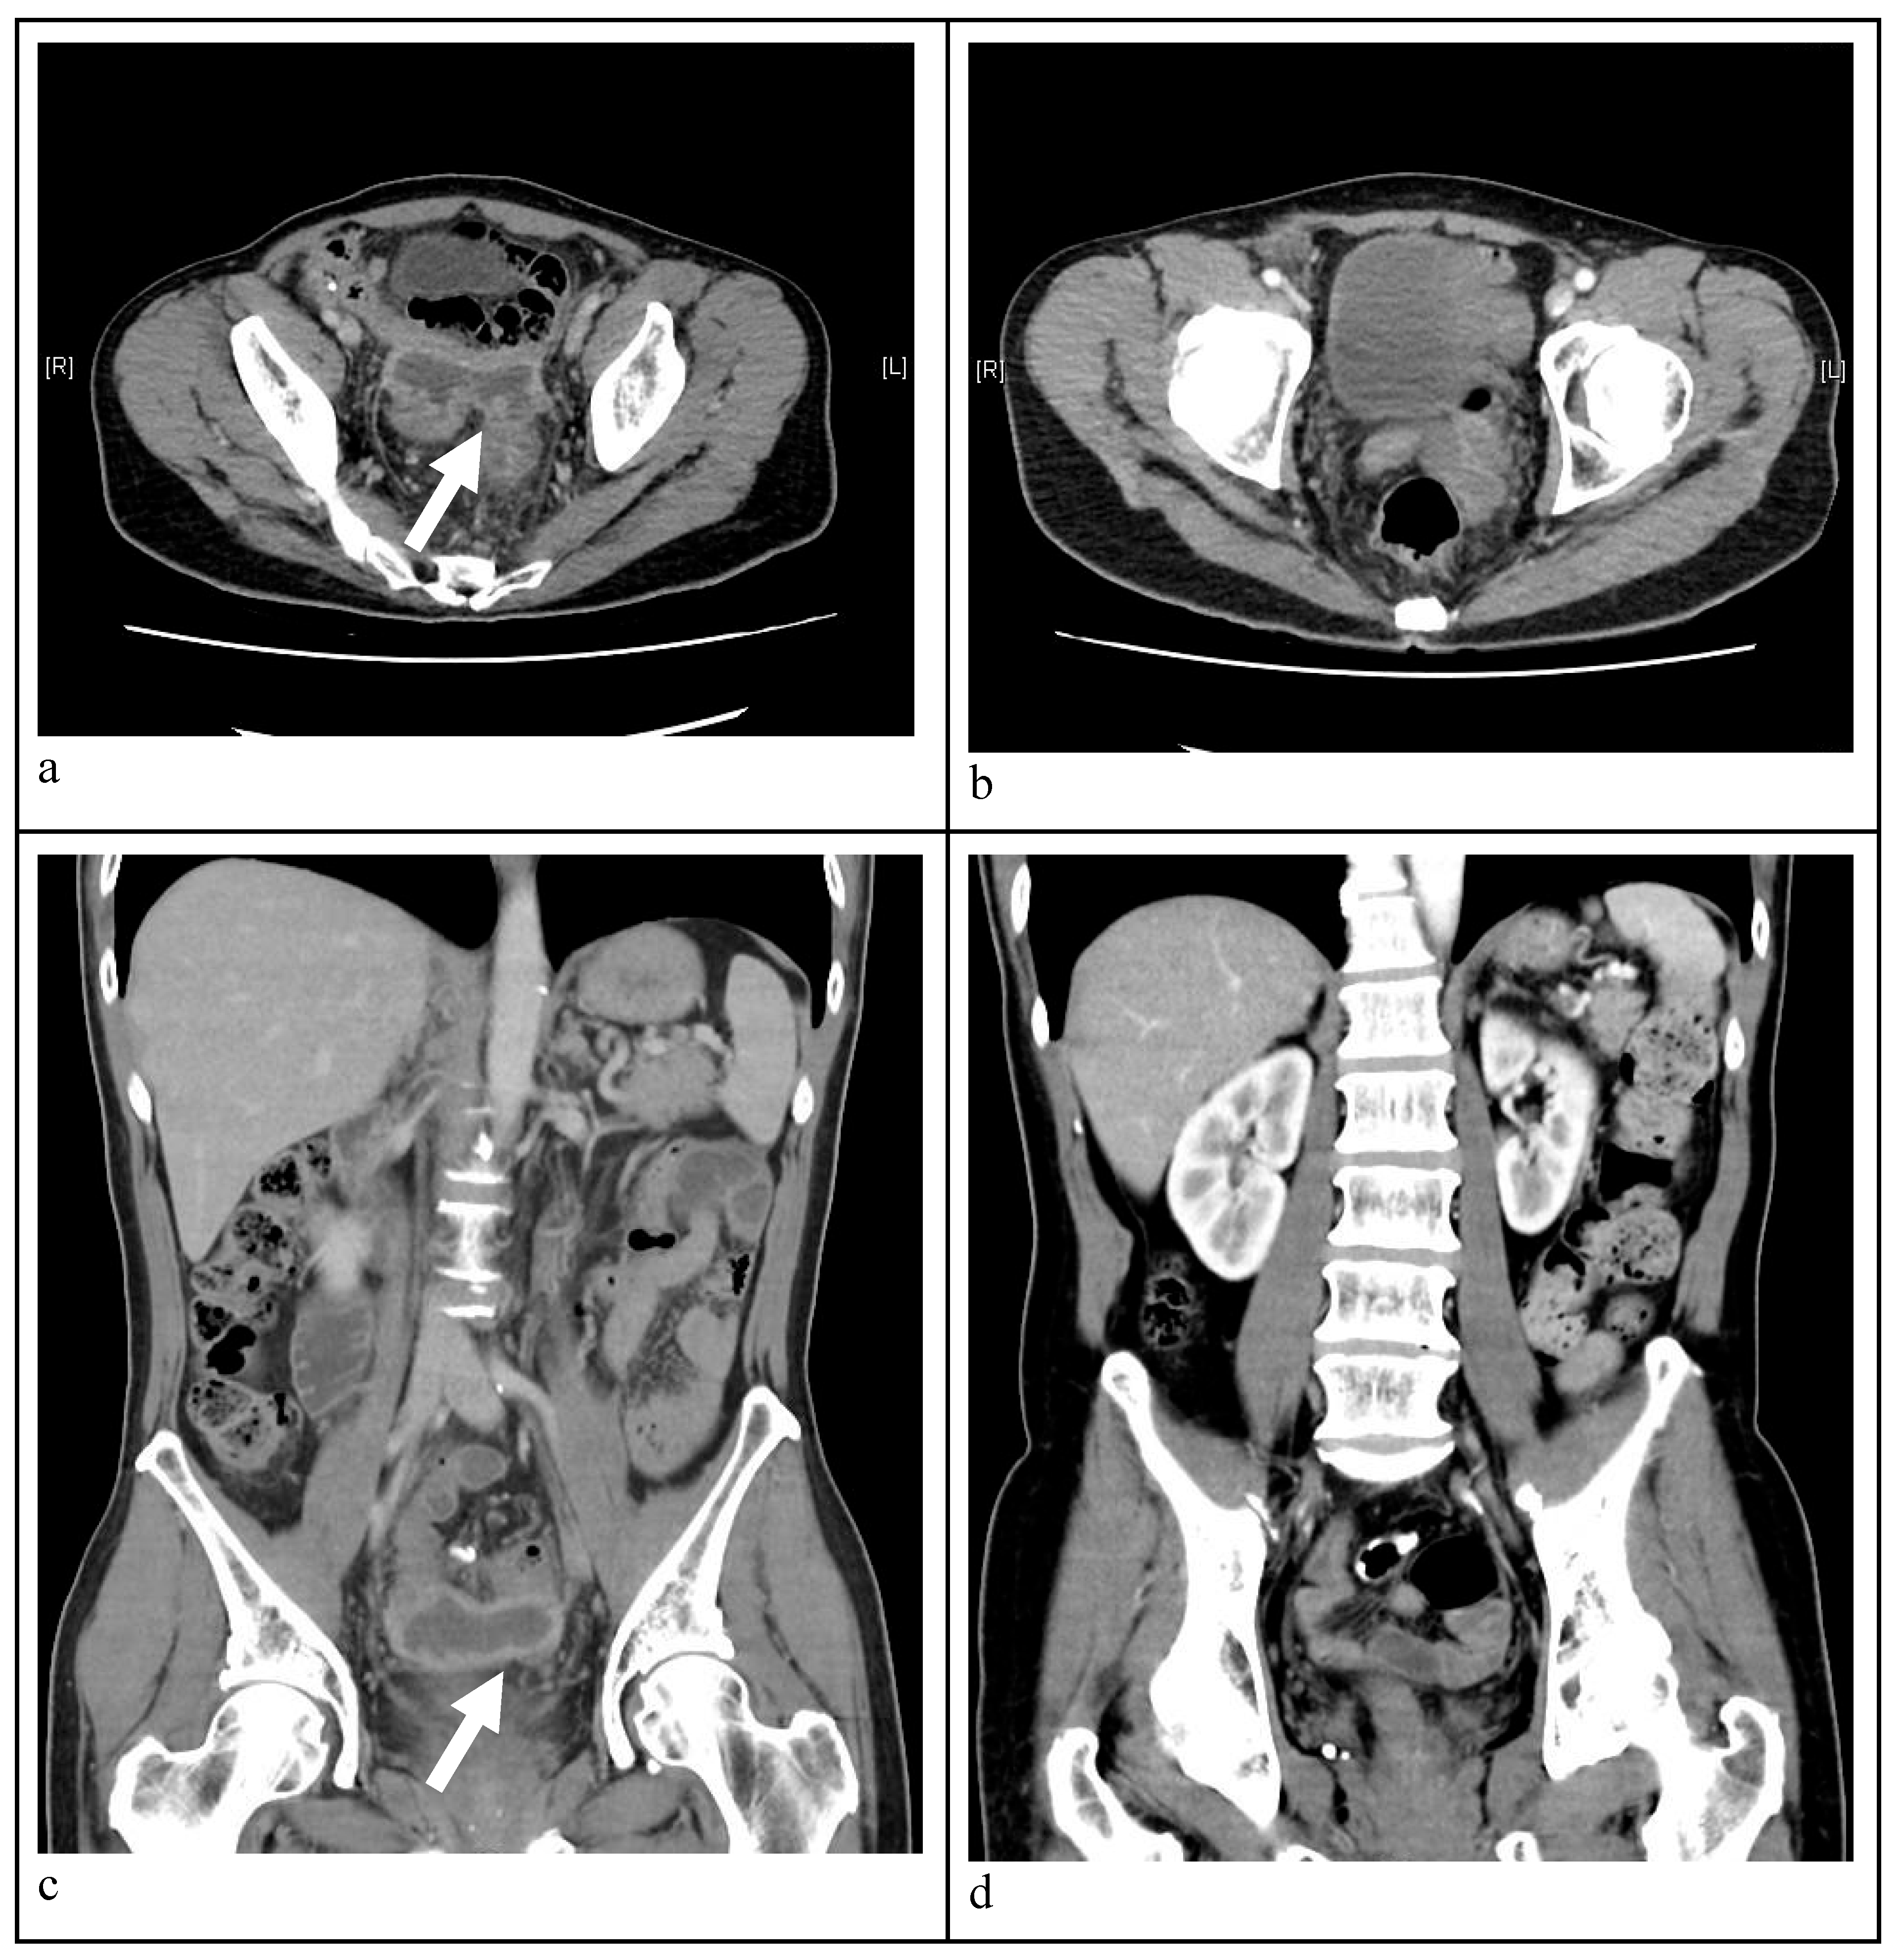

- Axial view CT image indicating a massive abscess occupying a significant portion of the intra-abdominal cavity. A well-circumscribed abscess fluid collection with enhanced walls is seen as pointed by the white arrows.

- Follow-up CT image disclosing no abscess and patent neovagina without perforation six months post-treatment.

- Sagittal view abdominal CT image demonstrating a intra-abdominal abscess. A well-circumscribed abscess fluid collection with enhanced walls is seen as pointed by the white arrow.